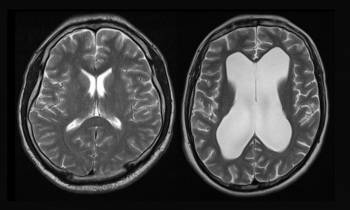

TECH | X-Pressure veut diagnostiquer l’hydrocéphalie

La jeune medtech toulousaine s’apprête à industrialiser son outil de diagnostic de l’hydrocéphalie avec le soutien financier de...